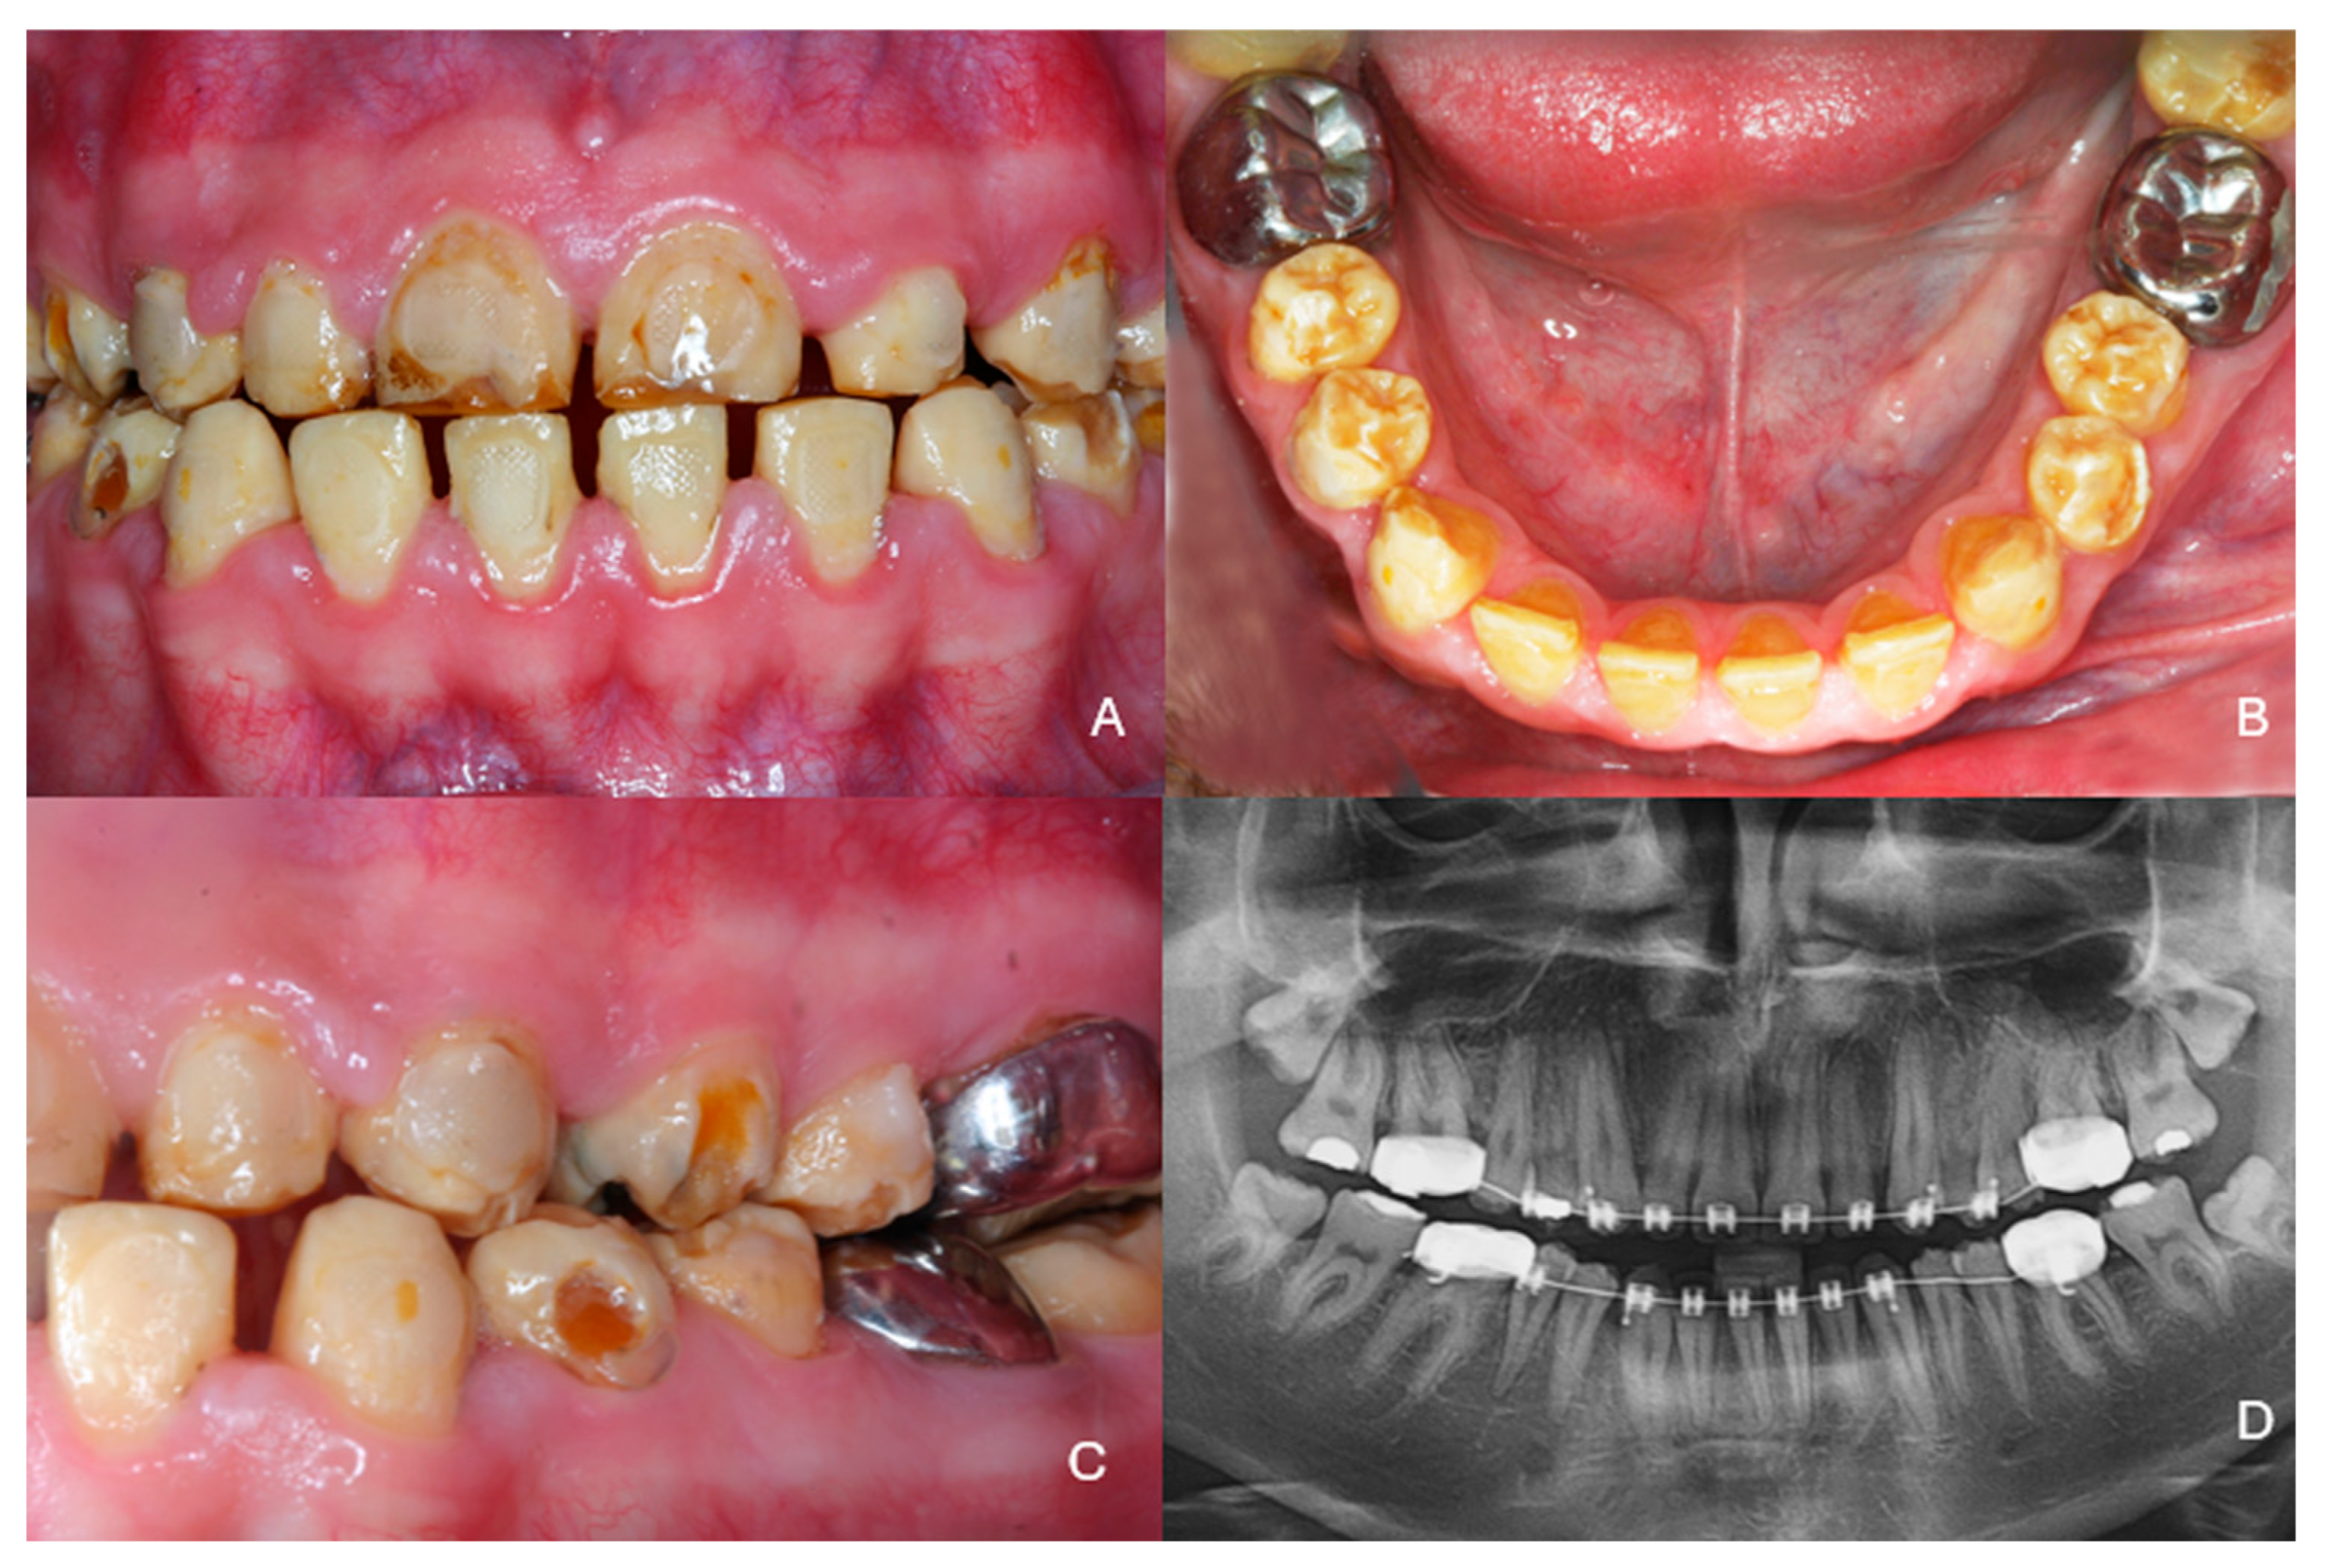

Full Mouth Rehabilitation with All-Ceramic Restorations in a Patient with Amelogenesis Imperfecta: A Case Report with 10-Year Follow-Up

2. Case Presentation